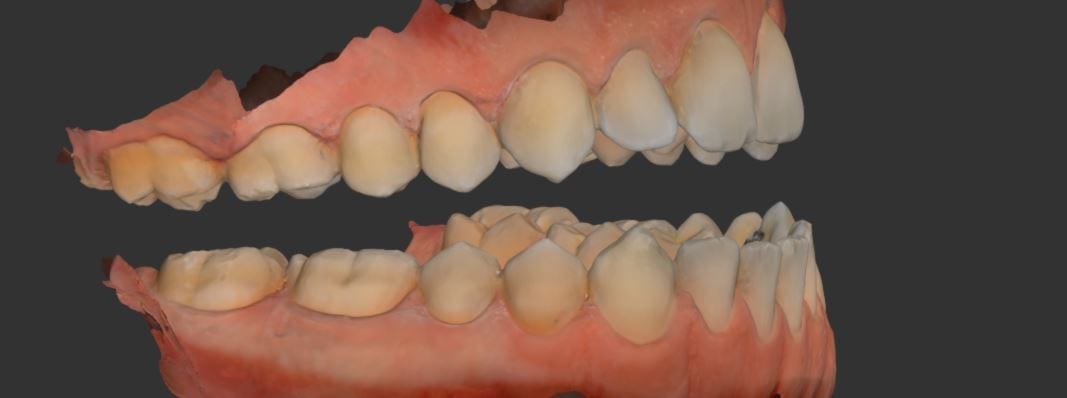

This is a case imaged for an occlusal guard, wehre the upper arch took only 43 seconds to capture. Afterwads, the lower arch is captured, and then ultimately we move […]